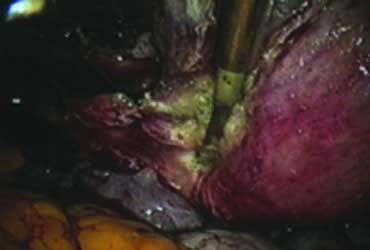

Amputation of the Uterus and Ablation of the Endocervix

After ligating both uterine arteries, the uterus becomes pale. At this time, the uterine body may be divided longitudinally using a shielded knife down to the cervix to facilitate morcellation. Each half is detached separately from the cervix 0.5 to 1 cm below the uterocervical junction and stored in the left upper abdomen. Alternatively, amputation of the uterine body off the cervix may be carried out through coagulation and cutting (above the ligated artery) proceeding from lateral to medial. The process may be initiated from the right or the left side. Bleeding points in the cervical stump are secured (Fig. 9). The upper portion of the endocervical canal is ablated circumferentially with bipolar coagulation (Fig. 10). Initially the walls of the cervix and the edges of the peritoneum were drawn together with sutures. This step was omitted, however, after noting at second look that the pelvic peritoneum heals without adhesions in the absence of sutures.

Fig. 9. Appearance of the cervical stump after uterine amputation.

Fig. 10. Ablation of the endocervix.